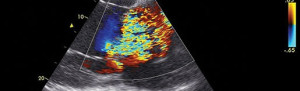

Beyond Basics: Practical Advanced Medical Ultrasound – A 1 ½-Day Practical Course